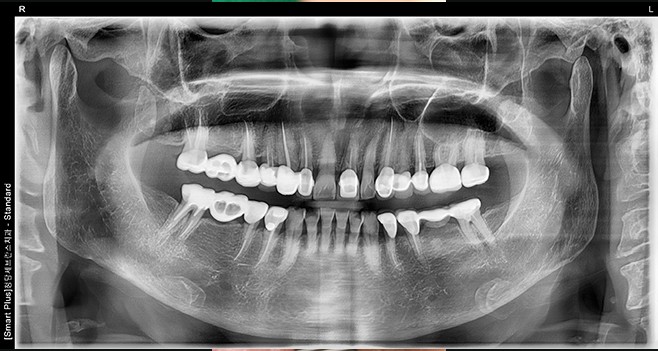

풀 셋팅 후 파노라마사진